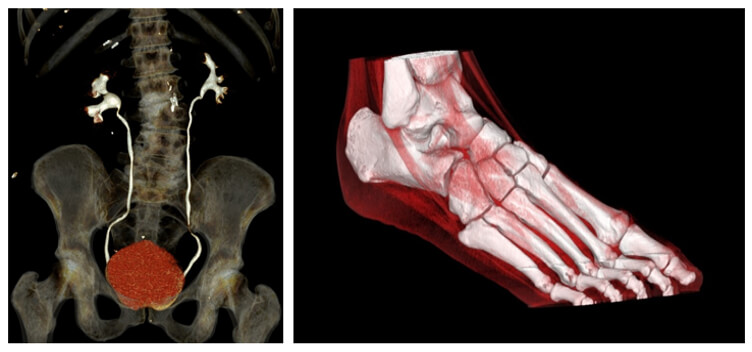

Volume Rendering

Volume rendering (VR) will allow us to use predefined protocols to adjust the amount of opacity and color applied to the model. Then you can display the table of results referring to the necessary measurements for prosthesis fabrication.

Density

Each density range has a very specific opacity coefficient (or transparency coefficient).

Volume Rendering and MIP

Volumetric MIP and ANGIO

The image on the left is post-processed using a volumetric maximum intensity projection technique.